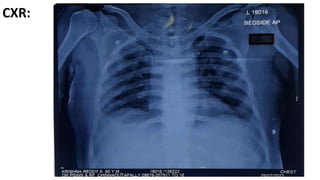

CXR:

• Pulmonology review was done i/v/o

CHEST x ray shows- Bilateral non- homogeneous opacities- ? Bilateral

Consolidation